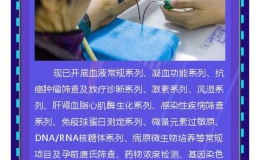

寿县济民医院临床检验中心造福一方百姓